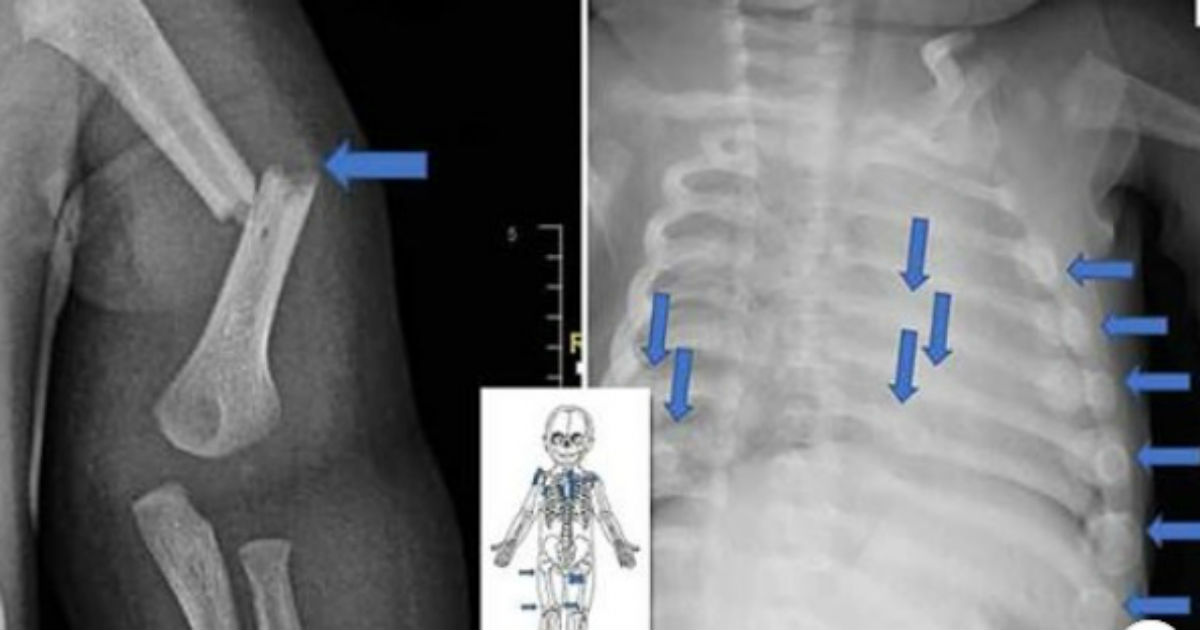

Porém, os médicos o examinaram e constataram que ele tinha mais de 20 fraturas nas costelas, nos dois joelhos e nos tornozelos. “Eles também perceberam que as fraturas foram causadas por força significativa de alguém”, disse o promotor Ryan Richter durante o julgamento.

Reprodução Polícia de Sussex – Algumas das fraturas que os pais causaram no bebê de quatro meses